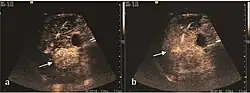

On CEUS examination, early HCC has an iso- or hypervascular appearance during the arterial phase followed by wash out during portal venous and late phase. There are studies showing that the wash out process is directly correlated with the size and features of neoplastic circulatory bed. Thus, highly differentiated HCC illustrates the phenomenon of late or even very late "wash out" while poorly differentiated HCC has an accelerated wash out at the end of arterial phase. It is therefore mandatory to analyze all these three phases of CEUS examination for a proper characterization of liver nodules. Tumor wash out at the end of the arterial phase allows the HCC diagnosis with a predictability of 89.5%. Some authors consider that early pronounced contrast enhancement of a nodule within 1–2 cm developed on a cirrhotic liver is sufficient for HCC diagnosis. These results prove that for a correct characterization of the lesions it is necessary to extend the examination time to 5 minutes or even longer.